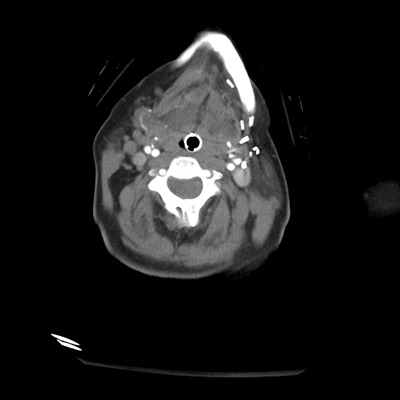

CTA head/neck

With the CTA of her head/neck, we can sort of see some atherosclerosis (though the images aren't windowed well for this). Importantly, though, we can see a rounded abnormality around the tip of the basilar/left PCA. This is an aneurysm! This helps put things together. This patient had an aneurysmal rupture leading to SAH and hydrocephalus, causing her loss of consciousness. While her leg extensor movements could be seizures, they're probably actually posturing movements, secondary to intracranial hypertension in the setting of her hydrocephalus.